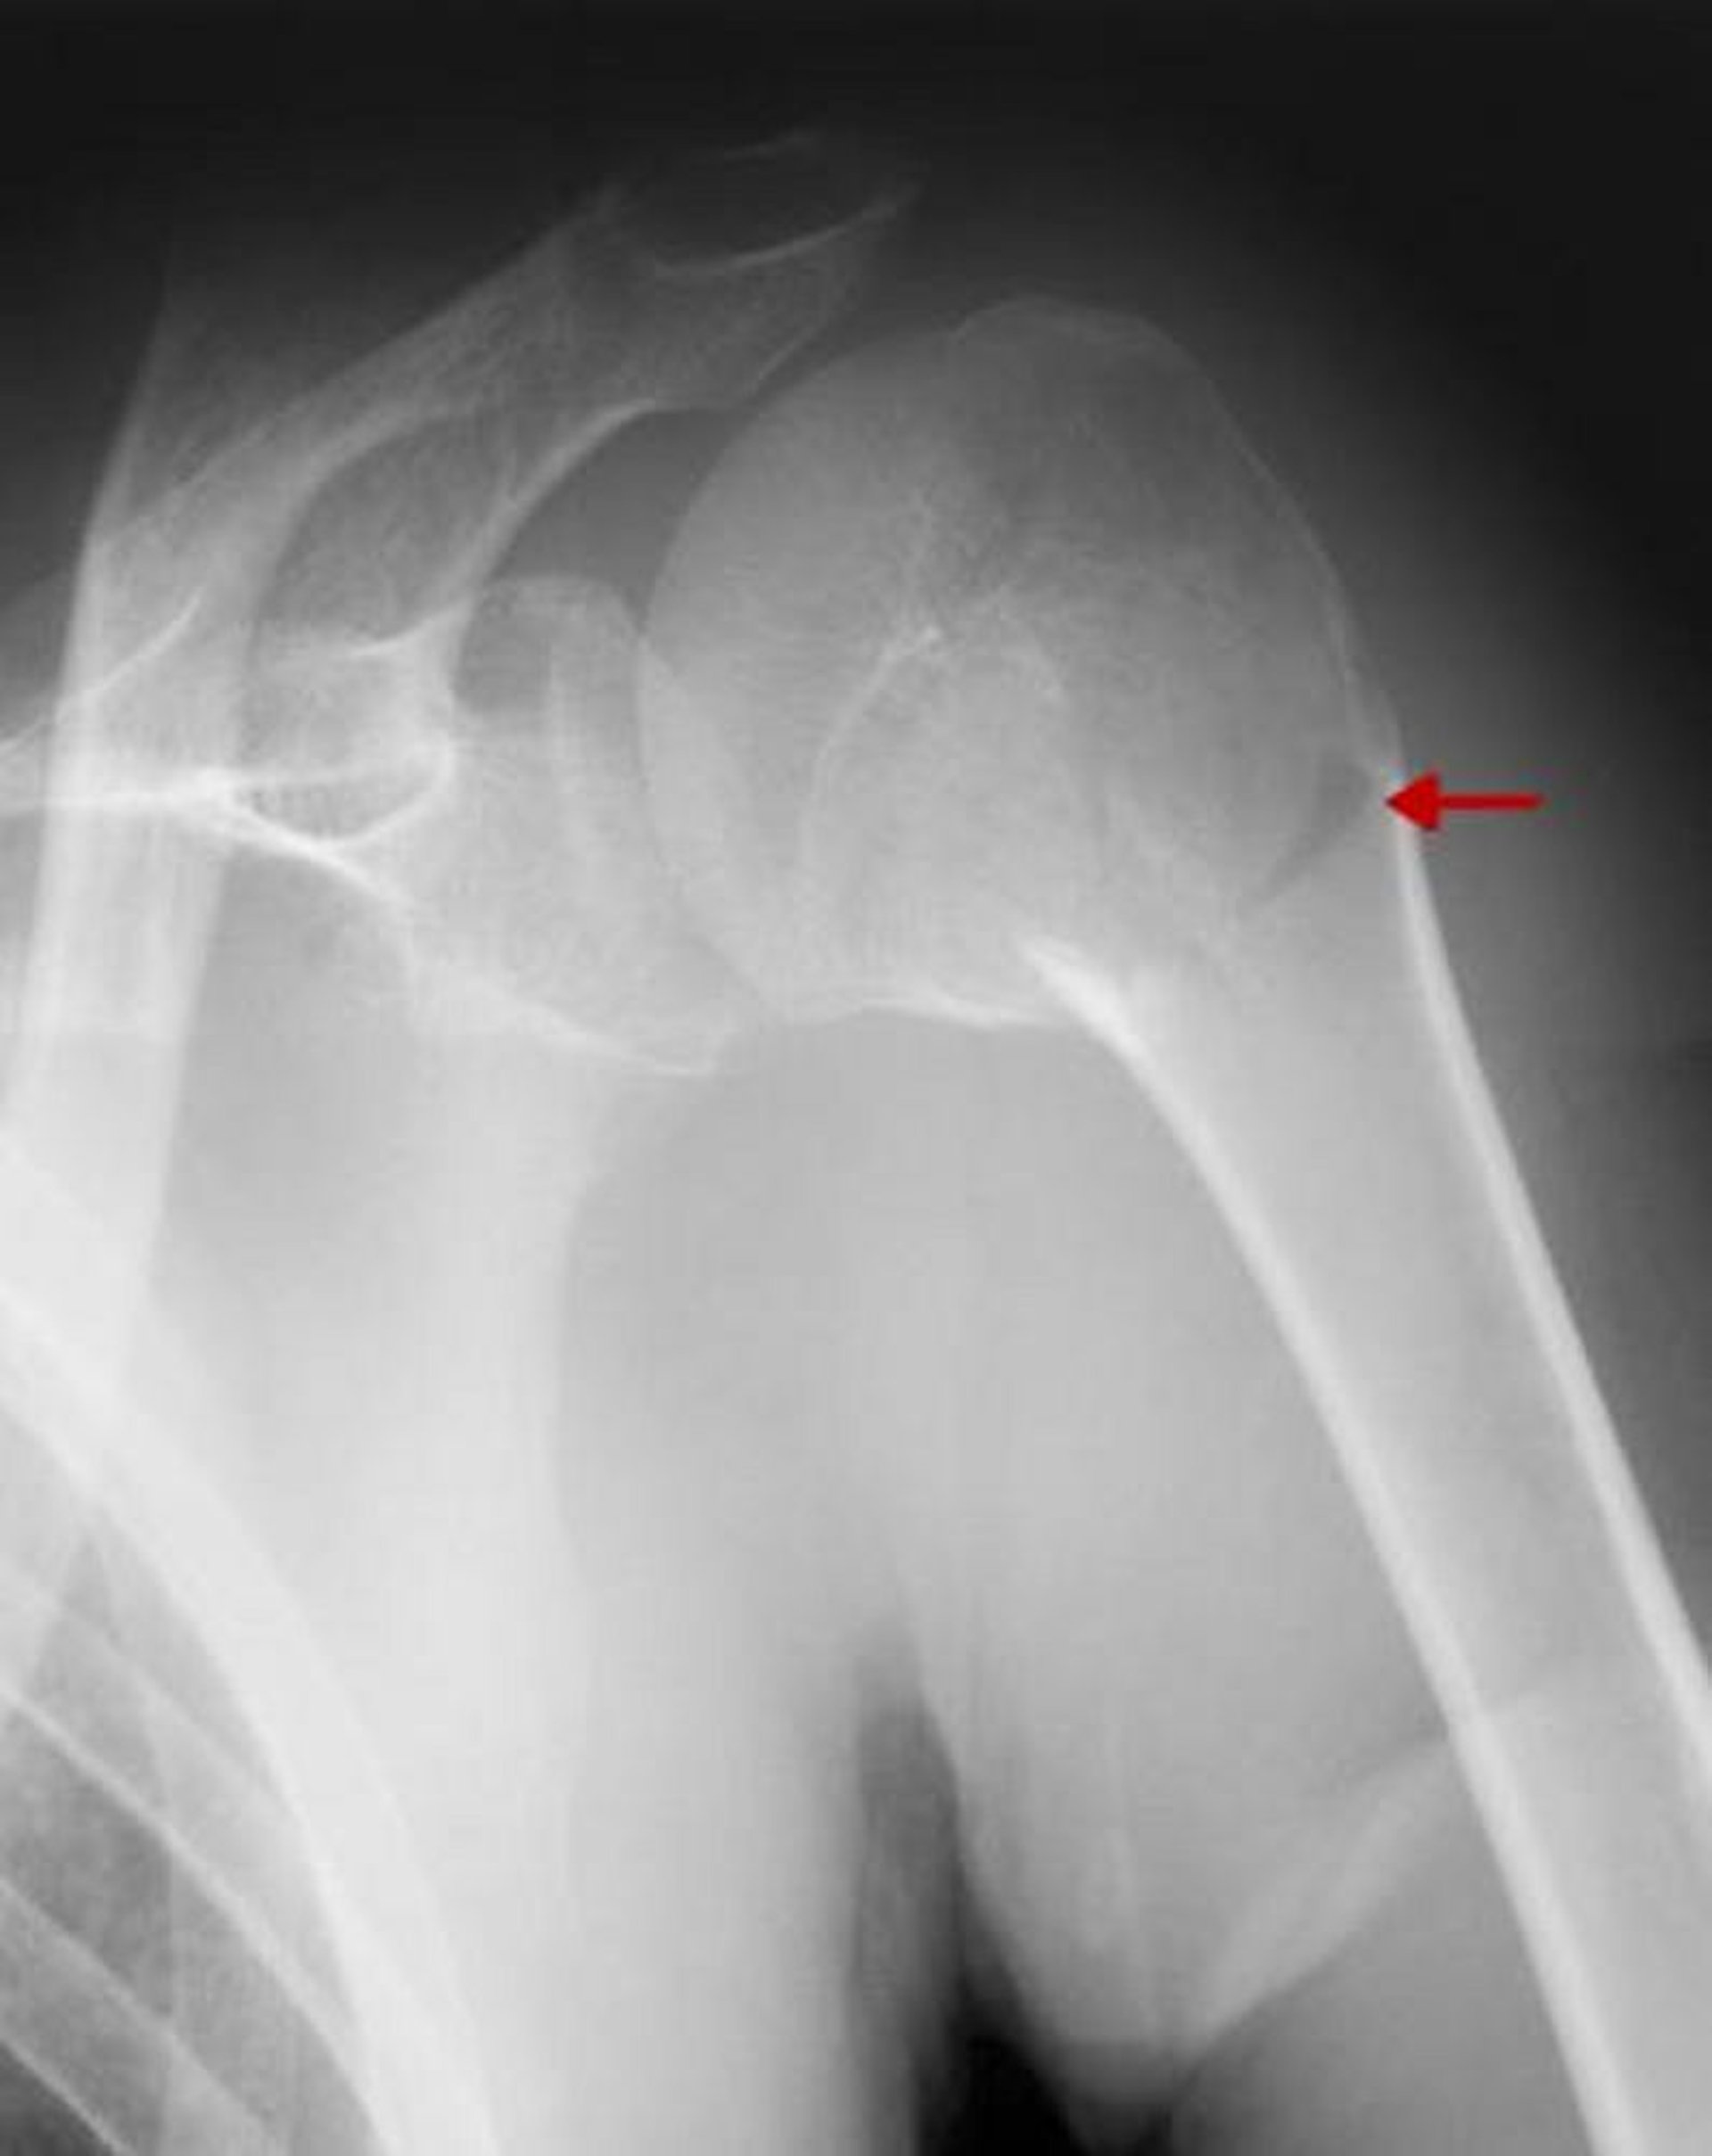

Diese Fraktur betrifft den Operationshals. Da keine signifikante Verschiebung oder Angulation > 45° vorliegt, handelt es sich um eine einteilige Fraktur.